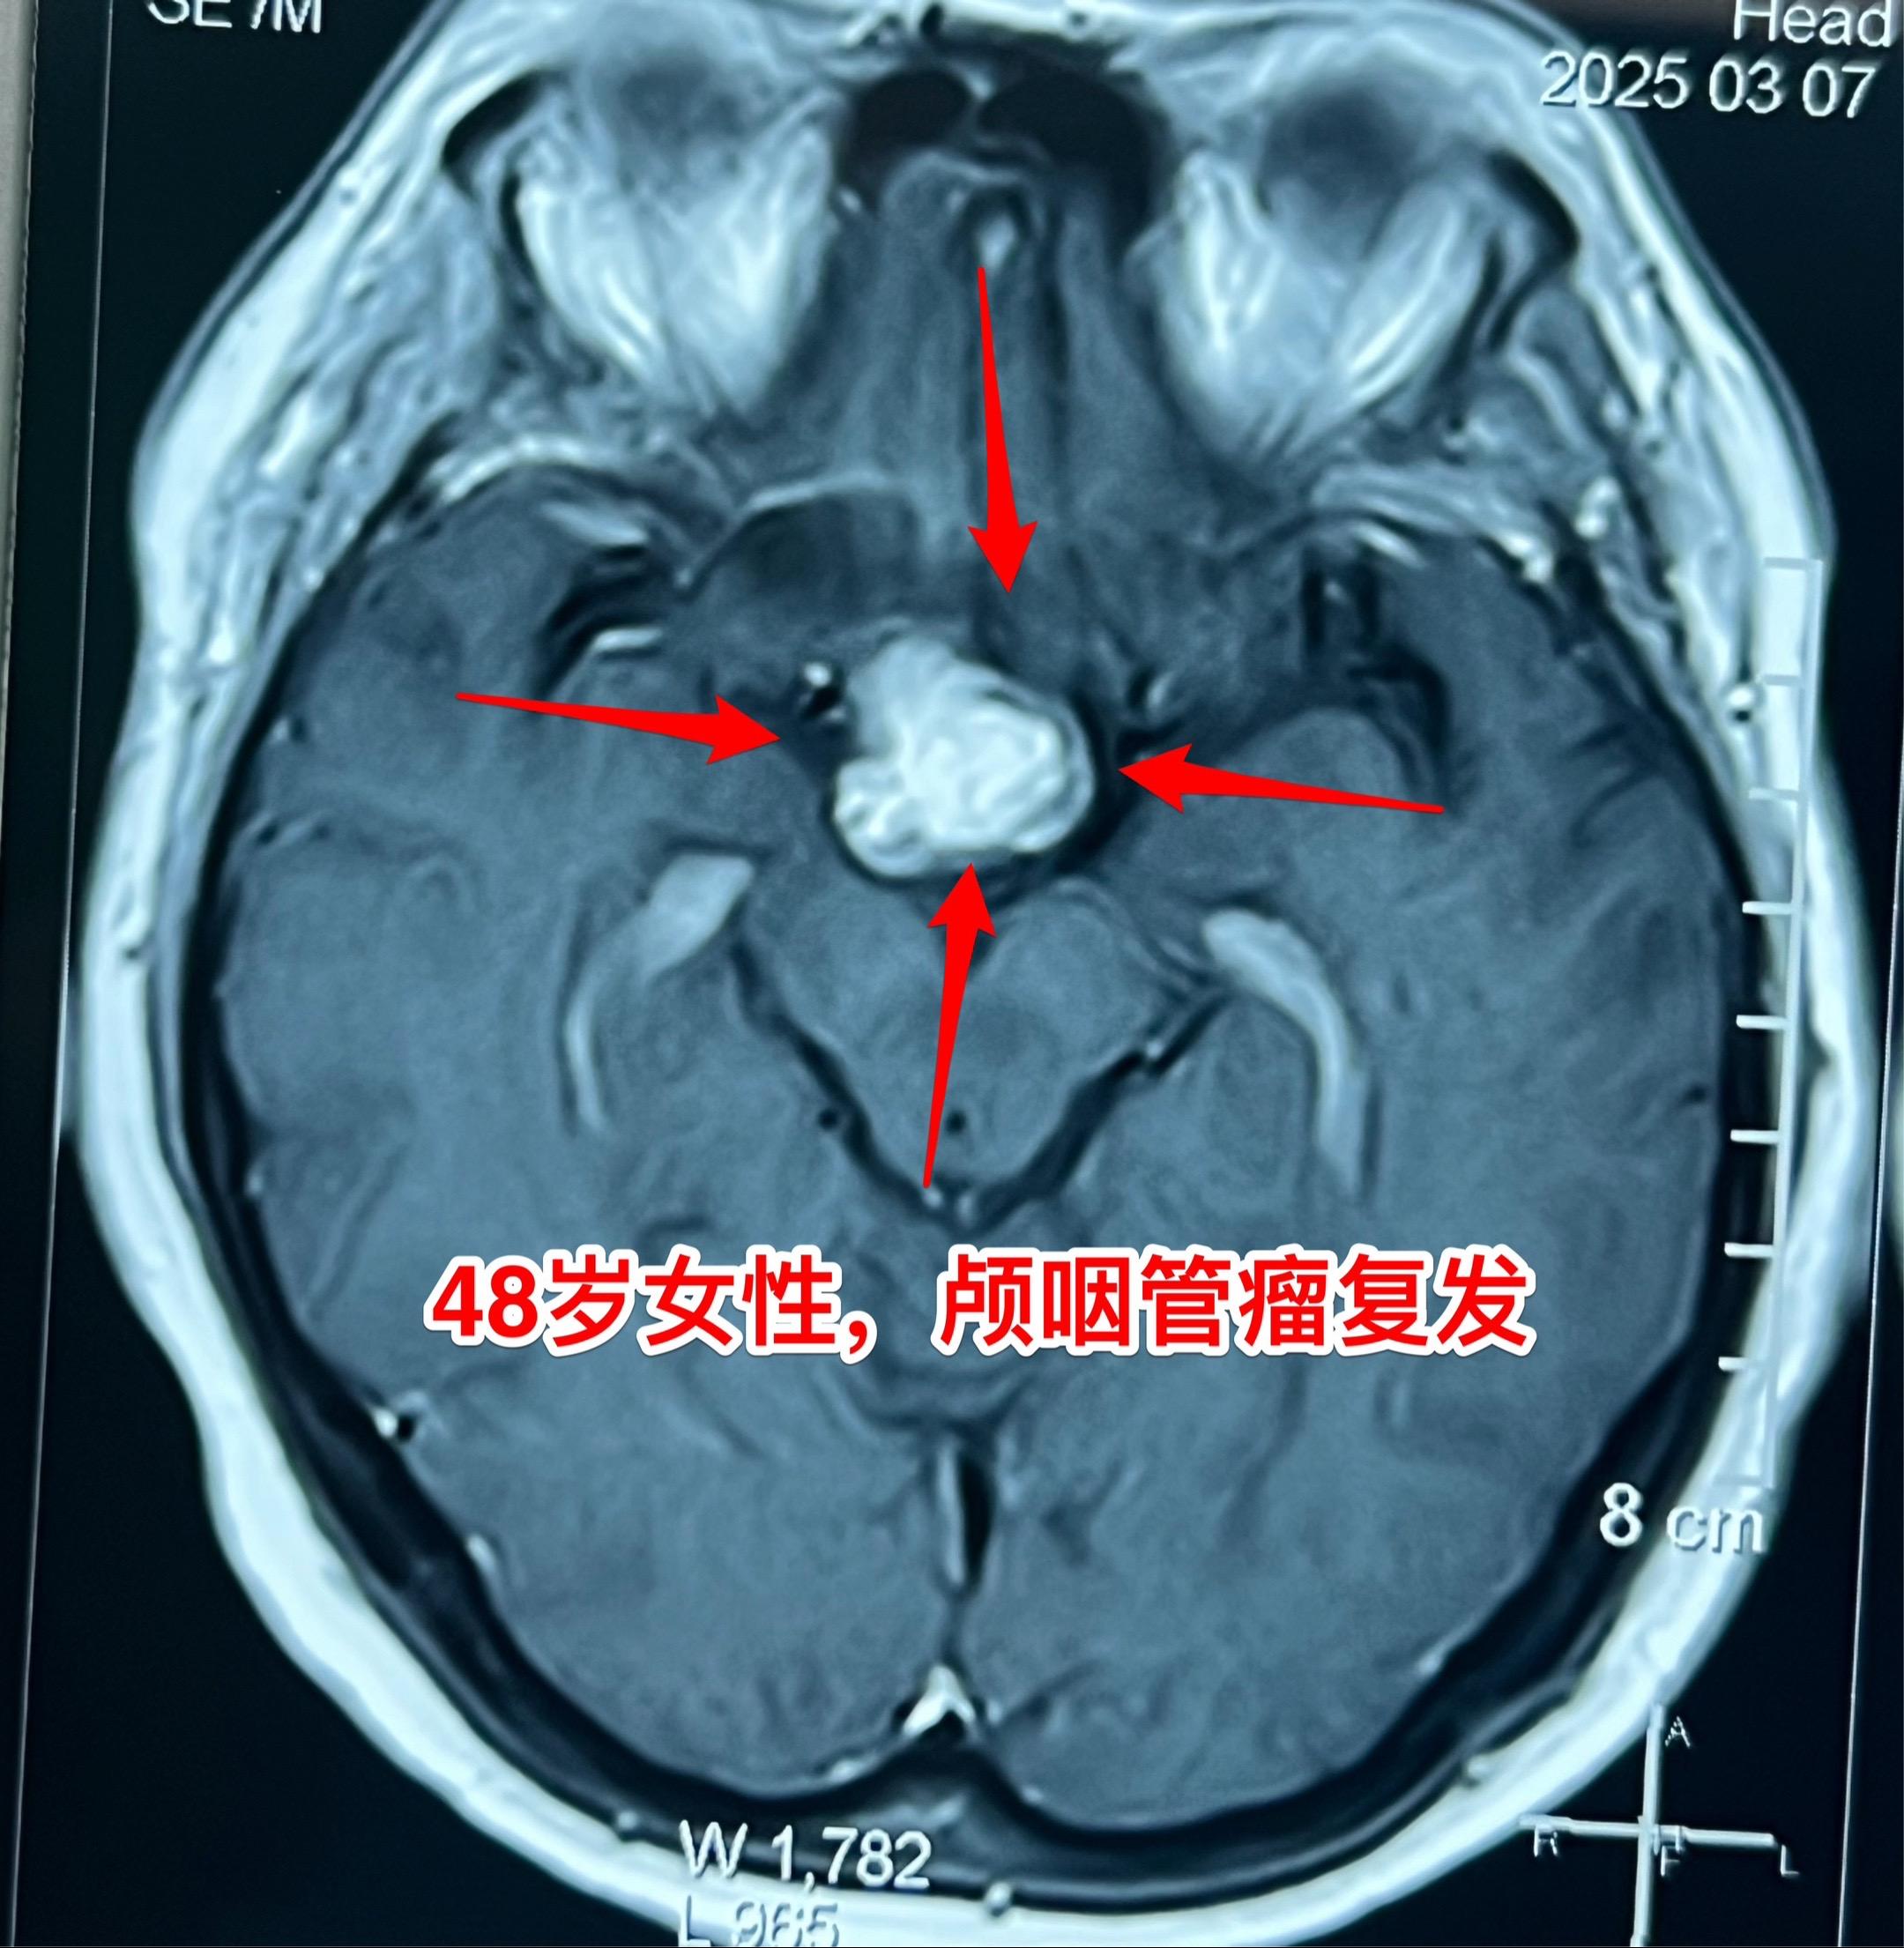

今天的第二个颅咽管瘤手术。48岁女性,洛阳市人。因颅咽管瘤先后行经鼻手术和开颅手术各一次。开颅手术是在24年12月作的,手术后又出现右眼视力下降,复查磁共振显示肿瘤复发,见图。 这个肿瘤看起来似乎难度不大,其实不然。距离前一次手术刚刚三个月,瘢痕粘连紧密而且肿瘤向左右两侧均嵌入视神经-颈内动脉缝隙内。这是乳头型颅咽管瘤,很有难度!